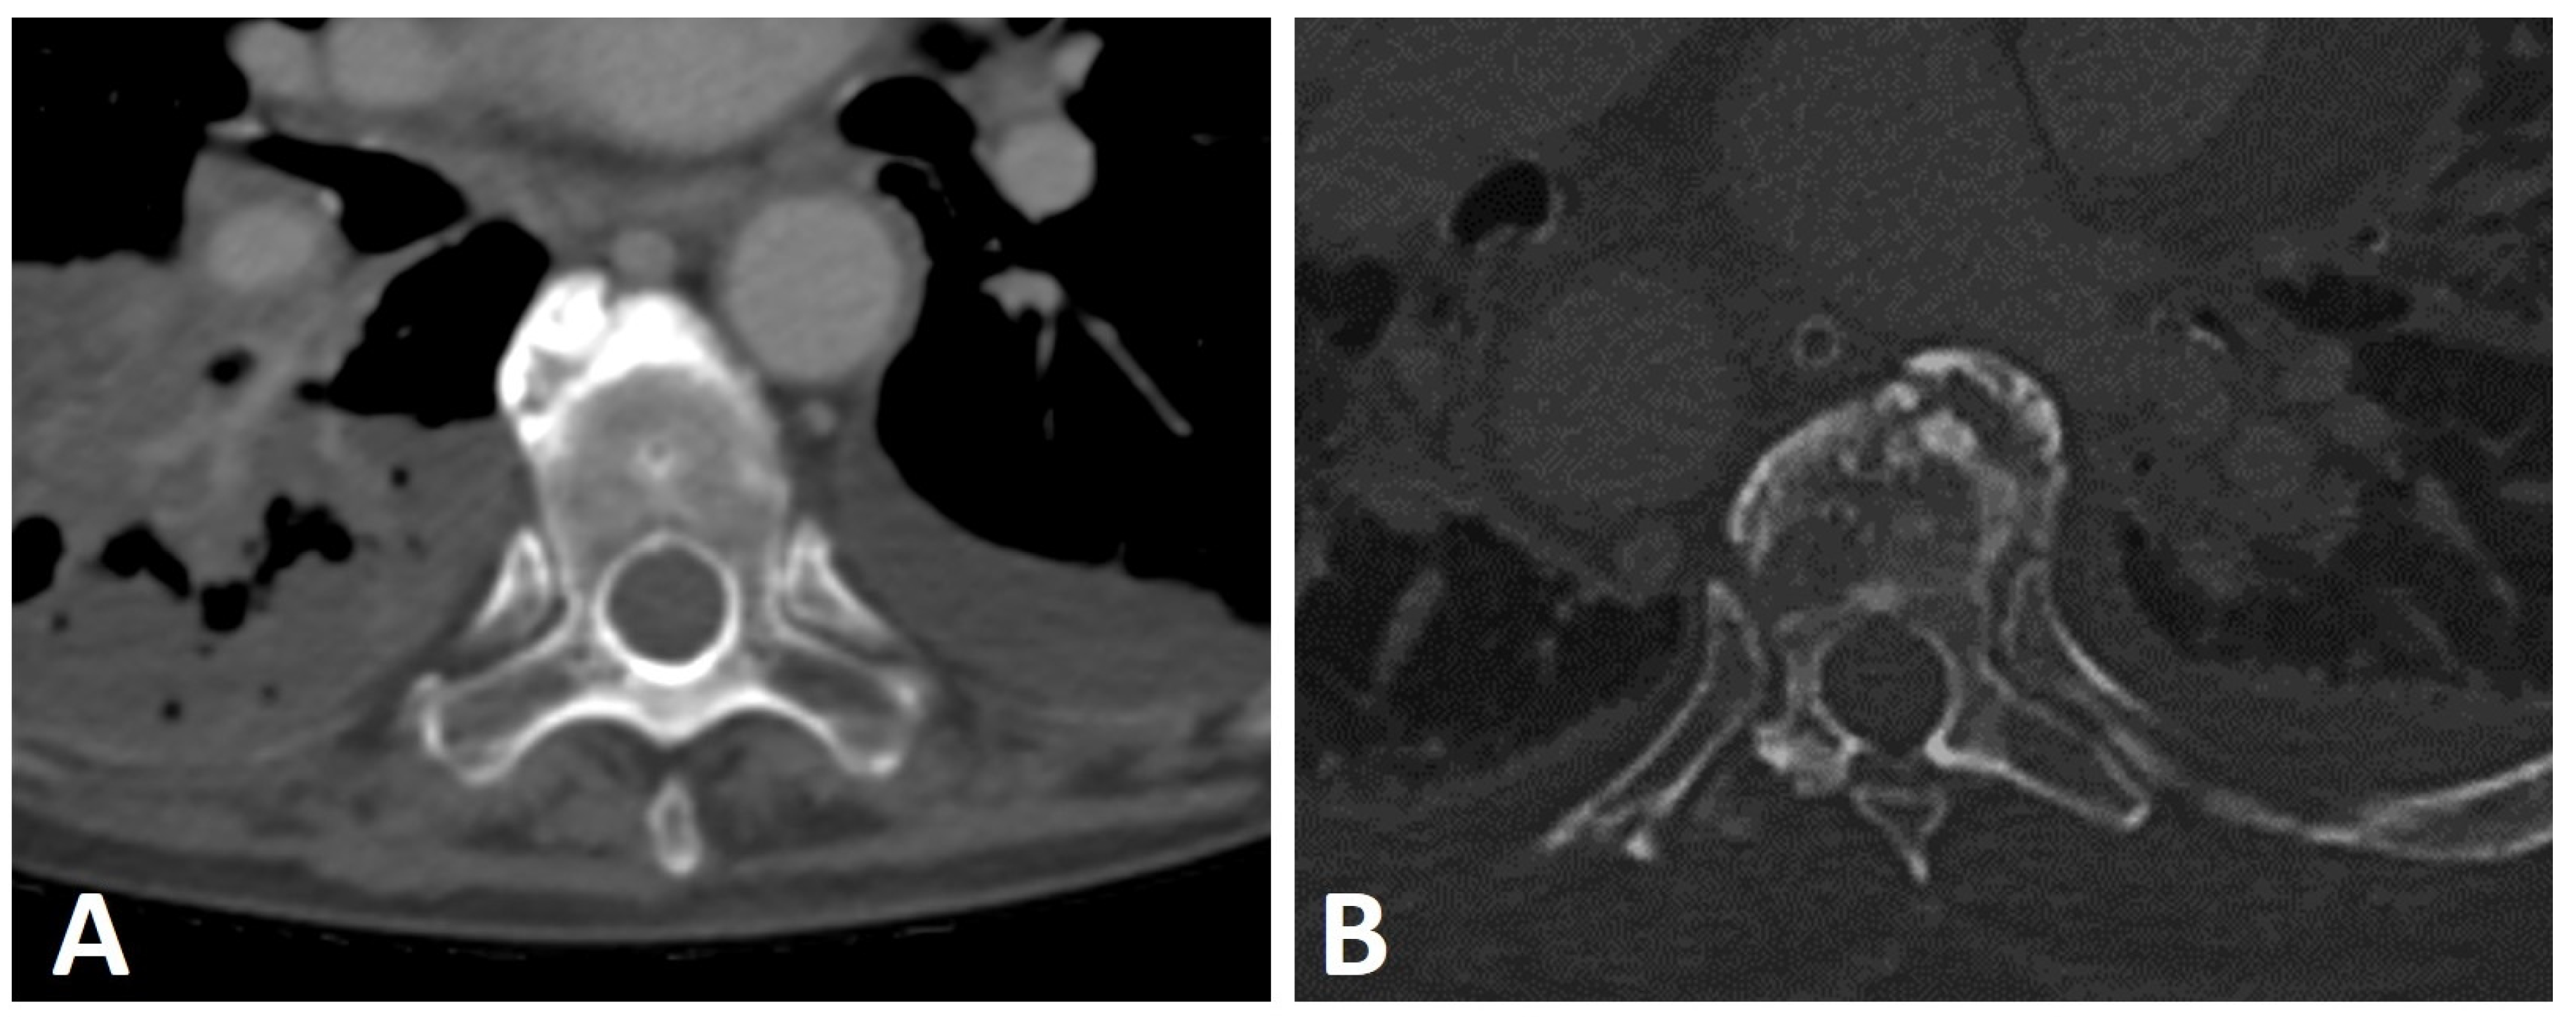

Bridging osteophytes in DISH are located along the anterolateral aspect of the vertebral bodies, most commonly involving the seventh through eleventh thoracic vertebrae [36,51,52]. These osteophytes are mostly detected on the right side of the spine, leading to the hypothesis that the pulsating, left-sided descending aorta inhibits new bone formation on the left [29,53]. Providing further validation of this hypothesis on the protective effect of the aorta, a previous study demonstrated the same effect in patients with the right-sided aorta, in which the majority of osteophytes were located contralateral to the descending aorta’s location (Figure 5) [25]. Moreover, a study on the location of syndesmophytes in subjects with AS reported the same reduced frequency of syndesmophytes at the vertebral rim near the aorta [54].

Figure 5.

Axial CT images of two patients with thoracic DISH (not shown). (A) left-sided and (B) right-sided aortas with an anterior osteophyte located contralateral to the aorta’s position.